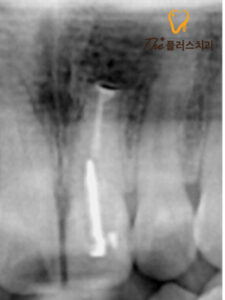

먼저 문제 치아의 뿌리를 절제하기 위해

잇몸을 박리한 후 염증을 제거하게 됩니다.

환자분의 경우 다행히 인접한 치아들까지

염증이 번지진 않았지만

해당 치아의 치조골이

상당부분 소실된 상태였습니다.

치아 뿌리 끝을 절제하며

염증 조직들을 제거한 모습을 보실 수 있습니다.

치근단 절제술을 진행하고 난 후에는

재 감염 방지를 위해 치과용 재료를

사용하여 마무리하게 됩니다.